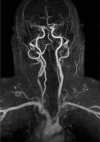

Results: Of the 160 IgG4-RD patients in this cohort, 36 (22.5%) had large-vessel involvement. The mean age at disease onset of the patients with large-vessel IgG4-RD was 54.6 years. Twenty-eight patients (78%) were male and 8 (22%) were female. Thirteen patients (36%) had primary IgG4-related vasculitis and aortitis with aneurysm formation comprised the most common manifestation. This affected 5.6% of the entire IgG4-RD cohort and was observed in the thoracic aorta in 8 patients, the abdominal aorta in 4, and both the thoracic and abdominal aorta in 3. Three of these aneurysms were complicated by aortic dissection or contained perforation. Periaortitis secondary to RPF accounted for 27 of 29 patients (93%) of secondary vascular involvement by IgG4-RD. Only 5 patients demonstrated evidence of both primary and secondary blood vessel involvement. Of those treated with rituximab, a majority responded positively.